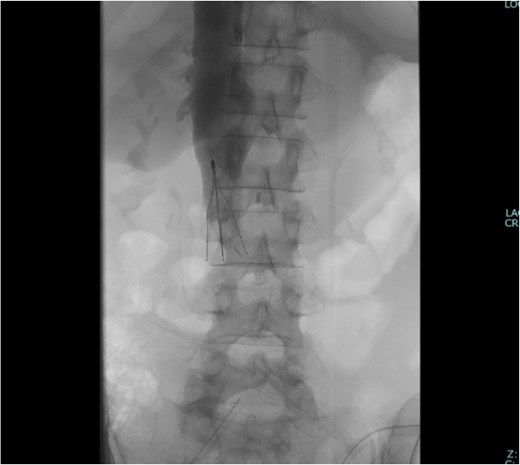

The surgical procedure was conducted with extracorporeal membrane oxygenation available as a backup, accompanied by continuous intraoperative right heart transesophageal echocardiographic monitoring. The surgical approach was a midline laparotomy. The ovarian tumor was successfully excised as there were no intraabdominal adhesions (Fig. 2A). The IVC was carefully exposed after tumor resection, with care taken to prevent thrombus detachment. The extent of the thrombus was confirmed via ultrasonography (Fig. 2B). The bilateral ovarian veins were controlled with vessel loops, and the IVC was subsequently clamped below the renal veins (Fig. 2C). A venotomy was performed, and the thrombus was extracted (Fig. 2D). After confirming the absence of a residual thrombus through ultrasonography, the venotomy was closed using 5-0 polypropylene sutures. The IVC filter was placed via the jugular vein after the abdomen was closed (Fig. 3).

Intraoperative findings. (A) The ovarian tumor did not adhere to the peritoneal cavity. (B) Intraoperative ultrasound revealed a thrombus extending to the IVC below the renal vein. The thrombus had high echogenicity at the periphery and low echogenicity internally. (C) The IVC was clamped below the renal vein. The bilateral ovarian veins were ligated with vessel loops (arrow). (D) The extracted thrombus measured 65 × 15 mm and was already organized.